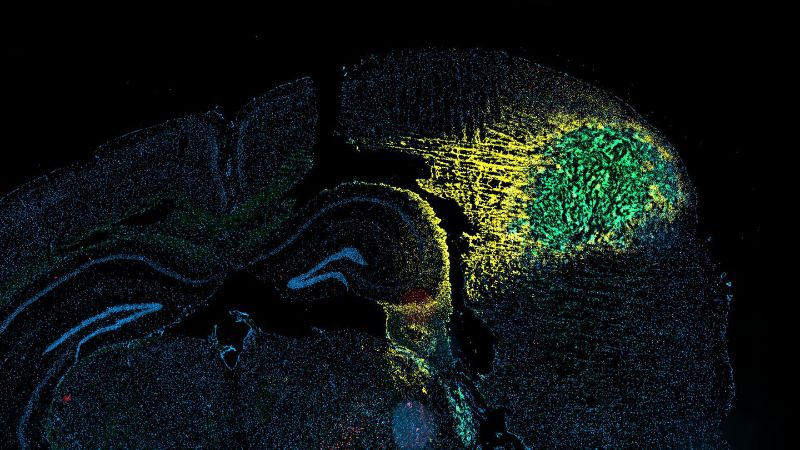

Cerebral tumor (glioma) of a mouse - 2023 EPFL / Michele De Palma - CC-BY-SA 4.0